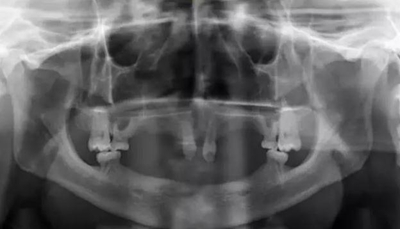

病例概要:患者,男,23歲,先天性多數(shù)恒牙缺失,外胚層發(fā)育不全,上下頜牙槽骨寬度及高度發(fā)育嚴(yán)重不足,佩戴傳統(tǒng)活動義齒固位穩(wěn)定效果差,幾乎沒有咀嚼功能,需通過種植修復(fù)來改善上述情況?;颊呒揖池毢?,所涉及的種植手術(shù)相關(guān)材料費(fèi)

用高,需要得到社會慈善機(jī)構(gòu)的幫助,才能獲得種植治療的可能。

病例資料:患者,男,23歲,先天性多數(shù)恒牙缺失,影響咀嚼和美觀功能。無恒牙拔牙史,無系統(tǒng)性疾病史,身體健康,無藥物過敏史。

??茩z查:口內(nèi)僅剩16,11,21,26,雙側(cè)上下頜乳牙E滯留,其余恒牙缺失,上下頜骨發(fā)育不足,缺牙區(qū)牙槽嵴呈刃狀,上下頜弓比例協(xié)調(diào)。CBCT顯示:上頜前牙區(qū)牙槽嵴寬度約2-3mm,骨高度約10mm;上頜后牙區(qū)可用牙槽骨高度僅1-2mm,左右側(cè)上頜

竇內(nèi)粘膜有明顯增厚。下頜牙槽骨寬度及高度嚴(yán)重不足,僅存有基骨。